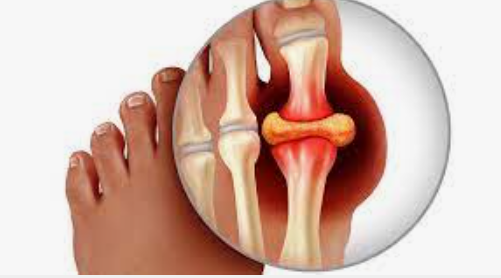

통풍은 일반적으로 한 번에 하나의 관절에 영향을 미치며 가장 일반적으로 엄지발가락에 영향을 미칩니다. 그러나 발목, 무릎, 팔꿈치, 손목 및 손가락과 같은 다른 관절에도 영향을 줄 수 있습니다. 통풍 증상은 보통 밤에 발생하며 종종 사람들을 잠에서 깨게 하며 중간 정도의 불편함에서 심한 통증에 이르기까지 다양합니다. 다음은 통풍 증상과 관련된 몇 가지 주요 내용입니다.

1. 심한 관절통: 통풍은 보통 한 번에 한 관절에 영향을 미치며 종종 엄지발가락 관절에서 시작됩니다. 통증은 일반적으로 시작된 후 처음 4~12시간 이내에 가장 심한 통풍 증상이 나타납니다.

3. 염증 및 발적: 영향을 받은 관절이 부어오르고, 압통이 생기고, 따뜻해지고, 붉어집니다.